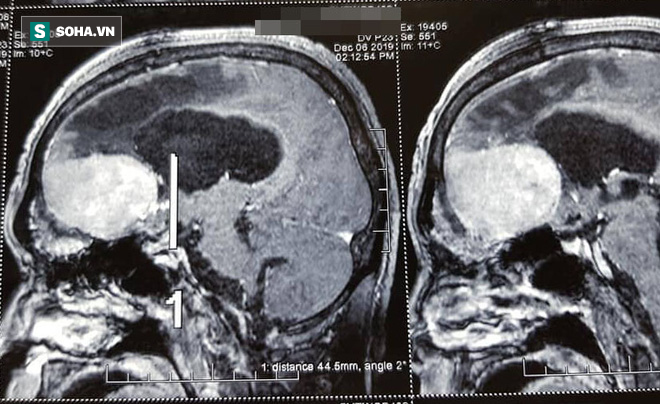

Sau khi, tiếp nhận bệnh nhân C các bác sĩ Bệnh viện Thanh Nhàn đã tiến hành chụp cộng hưởng từ phát hiện bệnh nhân có khối u não nền sọ trước đã xâm lấn xuống xoang sàng. Khối u rất nhiều mạch máu tân sinh, khi mổ phải cần thận.

Người đàn ông thoát cảnh điên dại sau nhiều năm, thủ phạm phát bệnh ít ai ngờ tới - Ảnh 1.

Khối u của bệnh nhân C.